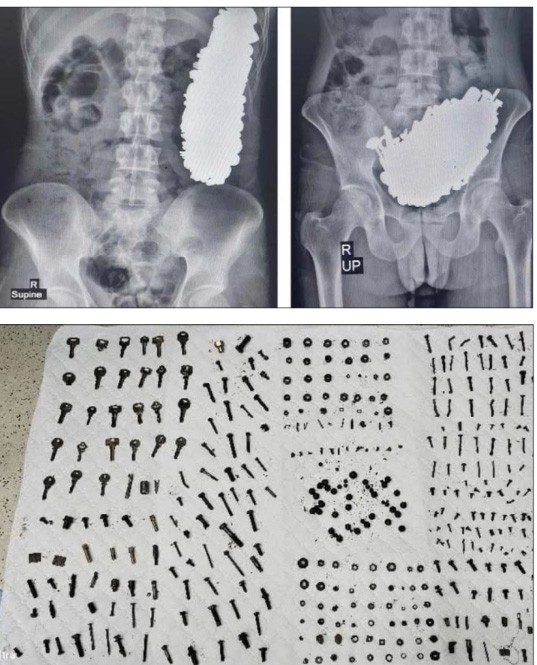

Lokal Despues di doló den su barika A saka tres kilo di metal for stoma di un hòmber August 26, 2024 FacebookTwitterPinterestWhatsApp E kontenido aki ta solamente pa abonado Registrá Already a member? Log in here